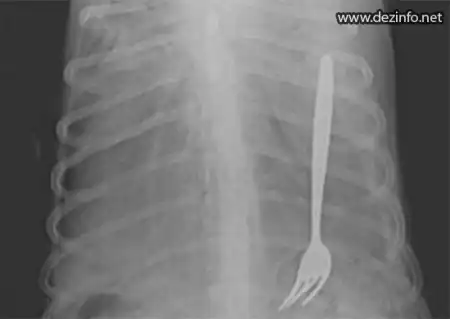

Вилку утащил с кухни и сdogeatел доберман Хаски.